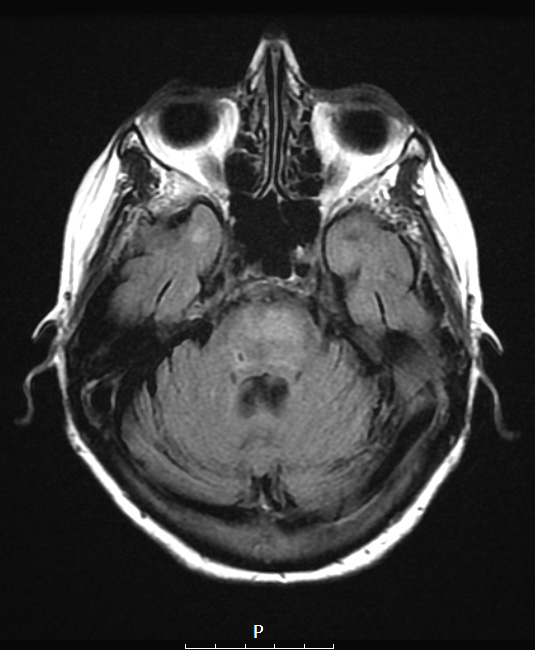

14A1 Lymphoma, Pons (Case 14) T2 FLAIR

This T2 FLAIR image shows a hyperintense mass within the basis pontis.